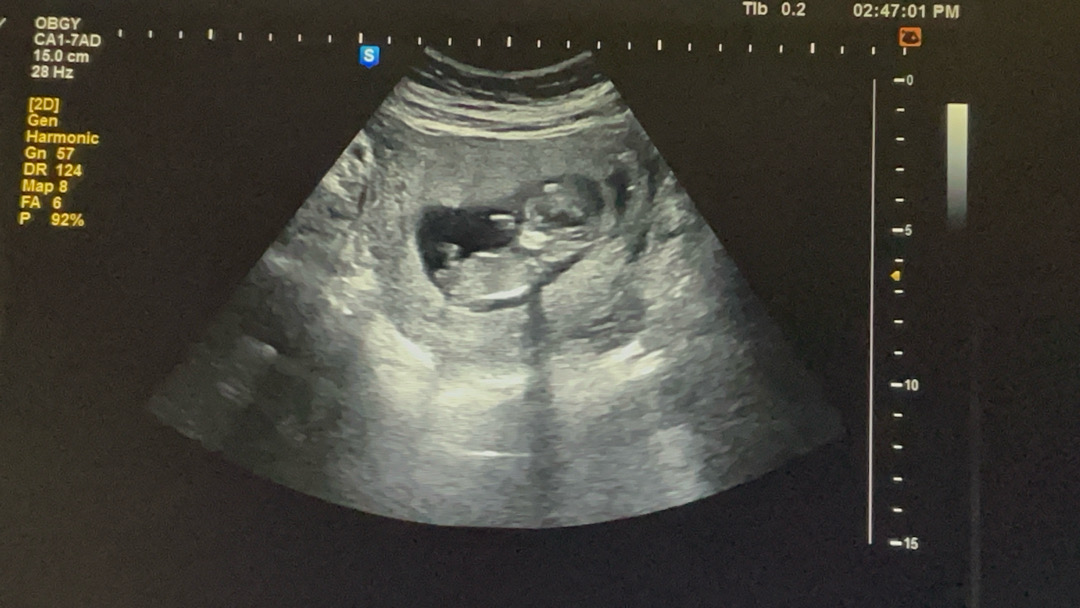

11주6일 각도법

봐주실분계신가용? 너무 궁금해용